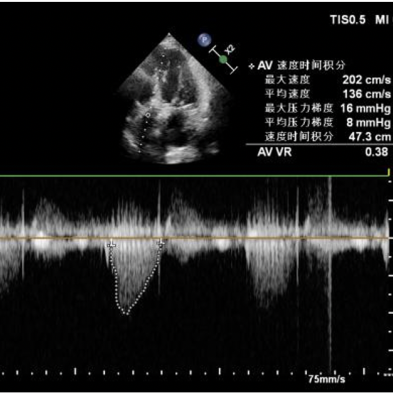

首次释放后发现植入位置不理想,利用VenusA-Plus®的可回收功能对瓣膜进行回收,重新精准定位后再次释放瓣膜。造影提示冠脉无阻塞,轻微主动脉瓣反流,无瓣周漏,术后即刻超声提示最大流速不足200cm/s,最大压差16mmHg,血压恢复至105/56 mmHg。术后患者状态恢复良好,已平稳出院。